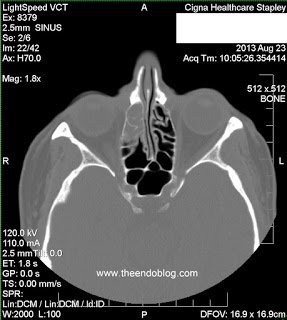

This patient presented to Arizona Sinus Center for evaluation of chronic sinus issues. She presented with chronic, unilateral nasal and facial symptoms, along with foul smelling nasal discharge. Nasal endoscopy was performed and findings include:

- RADIOGRAPHIC FINDINGS:

Endodontic diagnosis, including CBCT, determines that tooth #2 has a prior root canal with a root fracture and extraction is recommended. Tooth #3 has a prior RCT with apical abscess – caused by a missed MB#2 canal during the initial root canal treatment. Retreatment of the root canal #3 is recommended.